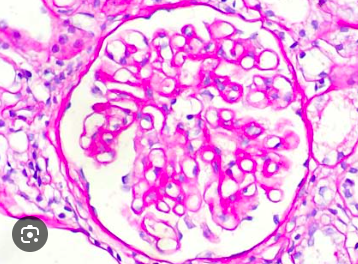

¿Qué es esto?

Glomérulo normal